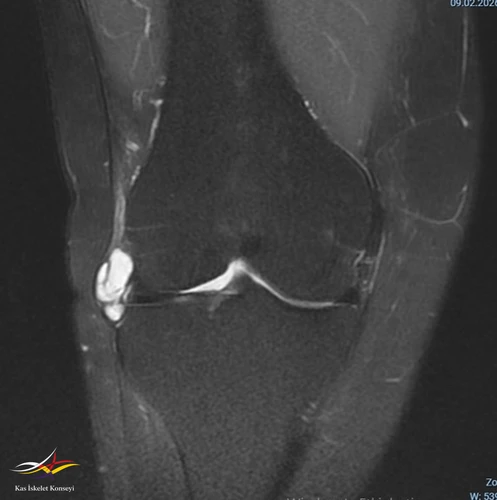

- Sağ diz MRG: Sağ diz ekleminde tibiofemoral ve patellofemoral eklem mesafeleri doğal olup, eklem yüzeyinde kartilaj yapı kalınlık ve sinyal intensiteleri tabiidir. Lateral menisküste longitudinal seyirli ve periferik uzanımlı rüptür ile lateral komşuluğunda LCL'yi deplase eden 22x32 mm boyutlu lobüle konturlu septalı parameniskal kist izlenmiştir. Medial menisküsün morfoloji ve sinyal intensite dağılımı doğal izlenmiş olup, patolojik sinyal intensite değişikliği saptanmamıştır. ACL, PCL'de hafif sprain mevcut olup, MCL, LCL tabiidir. Patellar ve quadriceps tendonların bütünlük ve sinyal intensiteleri tabiidir.

Resim 1. MRG koronal kesit.